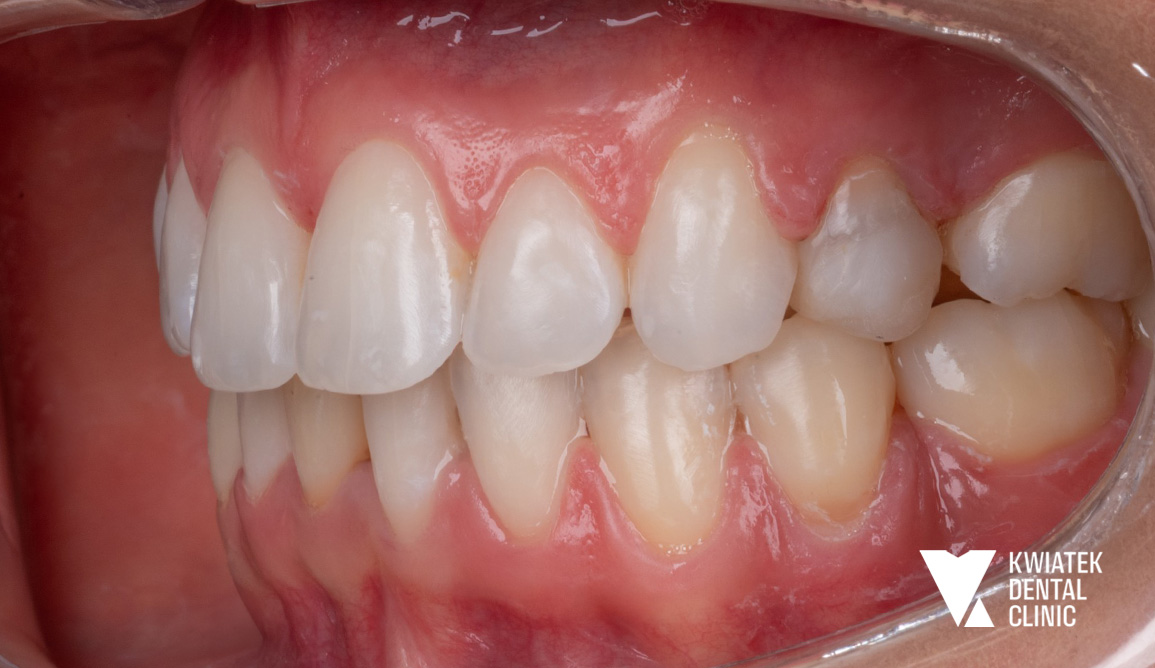

PO

Efekt końcowy to pełna metamorfoza uśmiechu zarówno pod względem zdrowotnym, jak i estetycznym.

Uzyskano:

• eliminację ognisk próchnicy i stanów zapalnych

• odbudowę funkcji zębów

• prawidłowe ustawienie zębów w łukach

• zamknięcie przestrzeni po ekstrakcjach

• poprawę relacji zgryzowych

• naturalny, harmonijny uśmiech